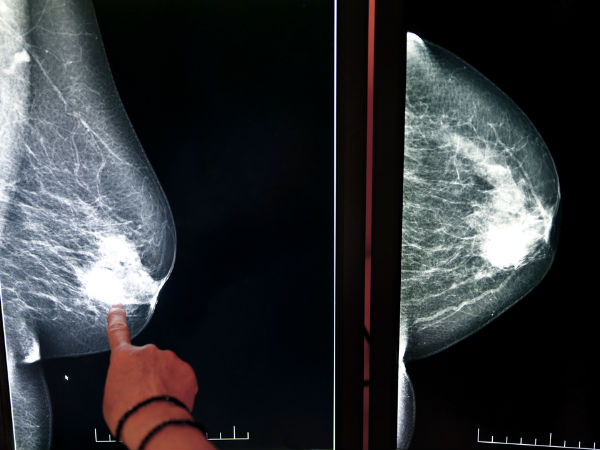

जानें, आपके ब्रेस्ट क्या कहते हैं आपकी सेहत के बारे में

आज कल महिलाएं अपने शरीर की सेहत को लेकर हर वक्त चौकन्नी रहती हैं। मगर कुछ महिलाएं शर्म और झिझक की वजह से अपने ब्रेस्ट के स्वास्थ्य के बारे में खुल कर बात करना पसंद नहीं करती।

ब्रेस्ट भी इंसान के शरीर का एक हिस्सा होते हैं, जो हर वक्त बदलाव महसूस करते हैं। ब्रेस्ट की केयर करना बेहद जरुरी है क्योंकि ये आपकी सेहत के बारे में ऐसे राज़ खोलेंगे जिन्हें शरीर के अन्य अंग नहीं बता पाएंगे।

यदि आपको खुद के ब्रेस्ट में छोटा सा भी बदलाव महसूस हो या फिर उनमें किसी प्रकार की असामान्यताएं दिखें तो, खुद को डॉक्टर को दिखाना ना भूलें क्योंकि यह किसी बड़ी बीमारी का संकेत हो सकता है।

आपके ब्रेस्ट का साइज, शेप, घनत्व, आदि, आपकी सेहत के बारे में क्या बताते हैं, आइये जानते हैं...

अगर आप अपने स्तनों में संवेदनशीलता, सूजन और कठोरता महसूस कर रही हैं, तो यह पीएमएस या गर्भावस्था के लक्षण हो सकते हैं। अगर इन दोनों की कोई संभावना नहीं है, तो आप को निश्चित रूप से स्तन कैंसर की जांच करवानी चाहिये।

क्या उनमें गांठ है?

अगर आप को ब्रेस्ट छूने पर गांठ महसूस हो तो यह या तो ब्रेस्ट कैंसर का संकेत हो सकता है या फिर कोई अन्य बीमारी का संकेत हो सकता है। इसके लिये आपको तुरंत जांच करवानी चाहिये।